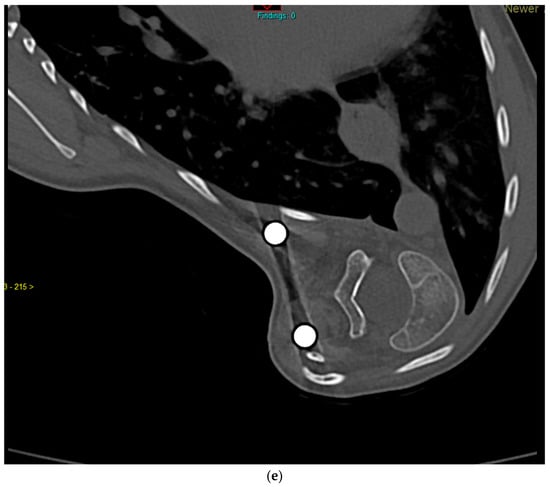

Previously Unreported TMEM38B Variant in Osteogenesis Imperfecta Type XIV: A Case Report and Systematic Review of the Literature

Osteogenesis imperfecta (OI) type XIV is a rare recessive disorder caused by TMEM38B pathogenic variants that disrupt an endoplasmic reticulum protein essential for calcium homeostasis and bone mineralization. This leads to severe bone fragility, early-onset fractures, skeletal deformities, low bone mass, scoliosis, and [...] Read more.

Osteogenesis imperfecta (OI) type XIV is a rare recessive disorder caused by TMEM38B pathogenic variants that disrupt an endoplasmic reticulum protein essential for calcium homeostasis and bone mineralization. This leads to severe bone fragility, early-onset fractures, skeletal deformities, low bone mass, scoliosis, and variable features like blue sclerae or dental abnormalities. We present a case report of a 21-year-old Italian male with a novel homozygous TMEM38B splice variant (c.112 + 1G > T), detailing the clinical presentation, genetic findings, and therapeutic outcomes. The patient exhibited multiple skeletal deformities and showed a moderate response to bisphosphonate therapy (neridronate). In addition, a systematic review of PubMed and Scopus identified 12 relevant studies from an initial set of 82 publications, encompassing data from 56 patients diagnosed with OI type XIV. Unlike classical collagen-related OI, TMEM38B-related OI necessitates genetic screening beyond classical collagen genes (COL1A1 and COL1A2). While bisphosphonates provide some clinical benefit, persistent fractures underscore the need for long-term management and innovative therapies. This case report and systematic review enhance understanding of OI type XIV and underscore the clinical importance of TMEM38B variants in bone fragility disorders. Full article